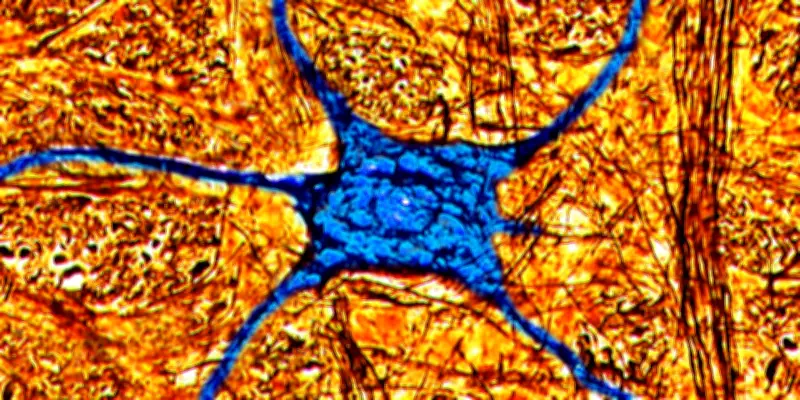

Une découverte scientifique majeure vient de bouleverser notre compréhension du vieillissement cérébral. Contrairement aux idées reçues, le cerveau humain conserve, chez certains individus âgés de plus de 80 ans, la capacité à produire de nouvelles cellules neuronales. Cette neurogenèse tardive, observée dans l'hippocampe, une région clé pour la mémoire et l'apprentissage, ouvre des perspectives inédites pour la recherche sur les maladies neurodégénératives.

Pendant des décennies, la communauté scientifique a largement admis que la neurogenèse, c'est-à-dire la formation de nouveaux neurones, déclinait fortement après l'enfance et s'arrêtait presque complètement à l'âge adulte. Les travaux récents, menés par une équipe internationale de chercheurs, démontrent le contraire. En analysant des échantillons cérébraux post-mortem de personnes octogénaires, les scientifiques ont identifié la présence de neurones immatures et de cellules souches neurales actives.

Ces observations indiquent que le processus de neurogenèse hippocampique peut persister tout au long de la vie, même à un âge avancé. Les chercheurs ont noté des variations significatives entre les individus, suggérant que des facteurs génétiques, environnementaux ou liés au mode de vie pourraient influencer cette capacité.